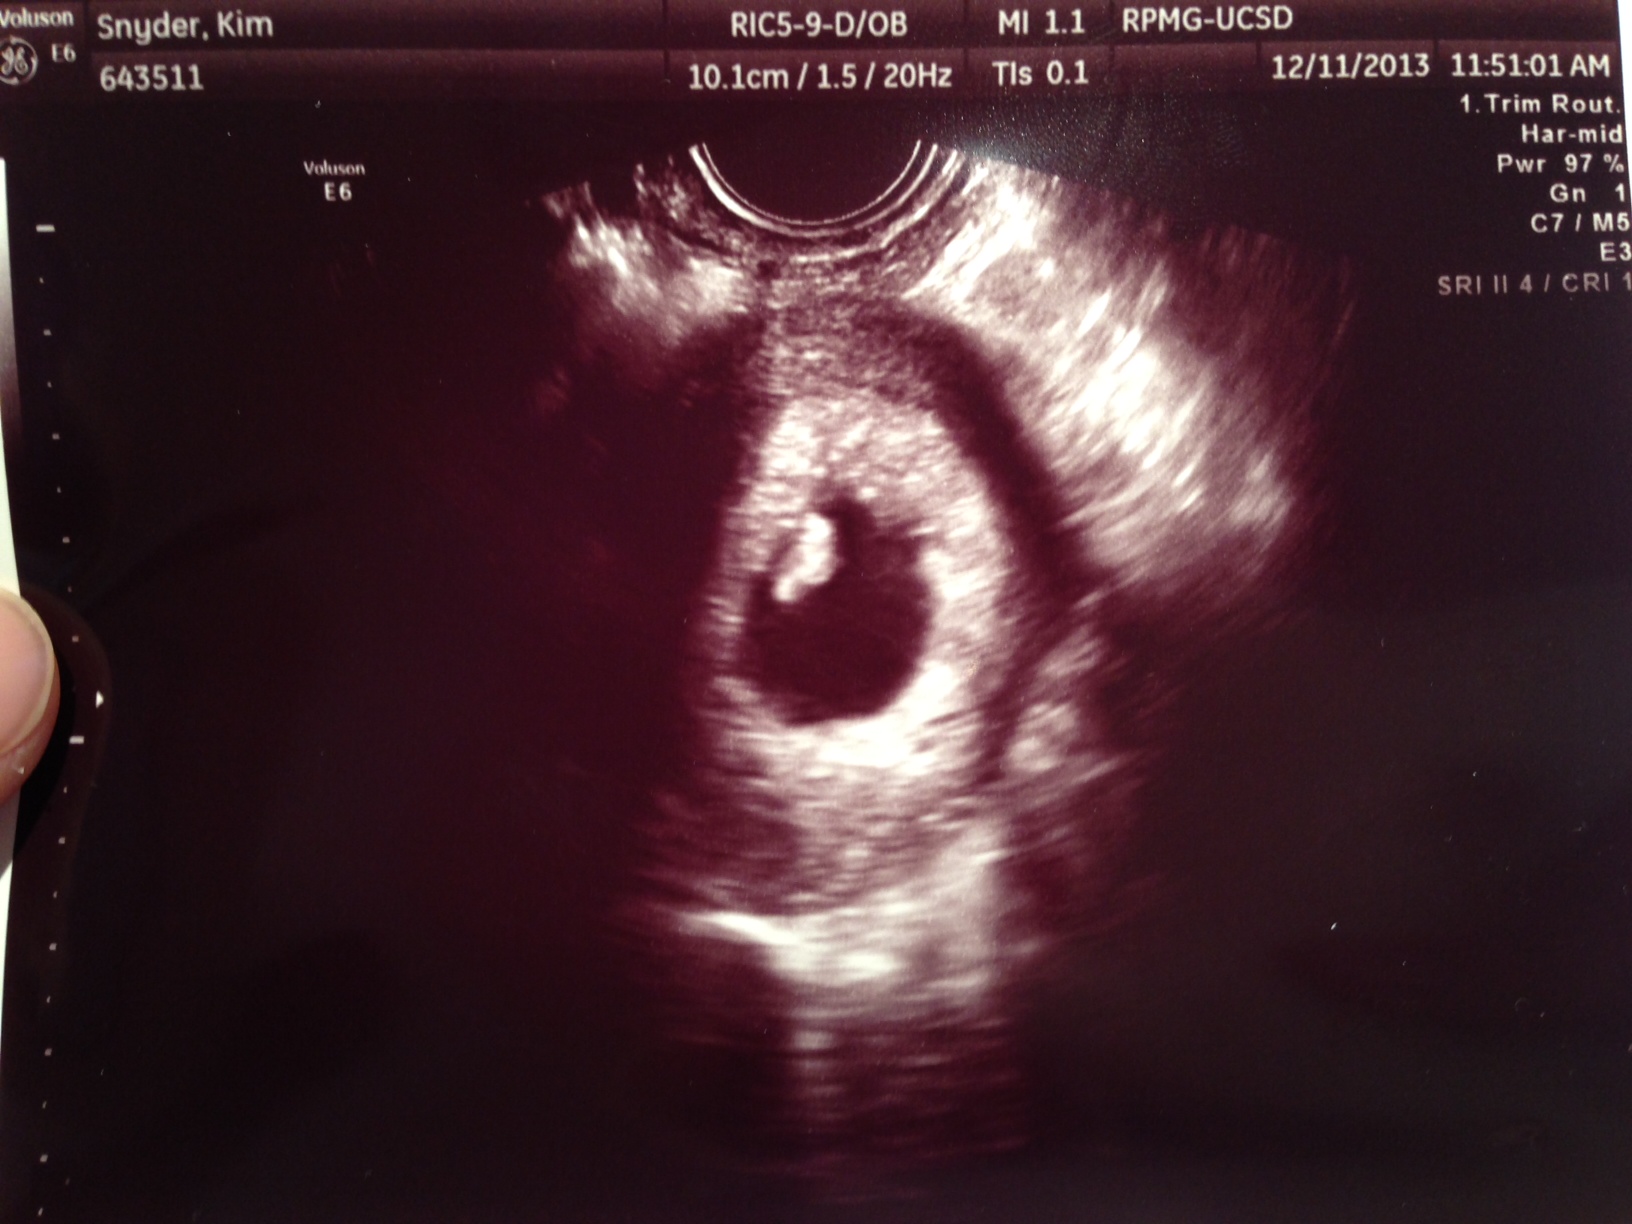

My Tuesday ultrasound was rescheduled twice. I have still been spotting/lightly bleeding on and off, I finally head to the Dr. in a few hours where hopefully they can assure me that everything looks fine. I will also have my blood drawn and if my levels look good I can stop all my meds, hell to the yes!